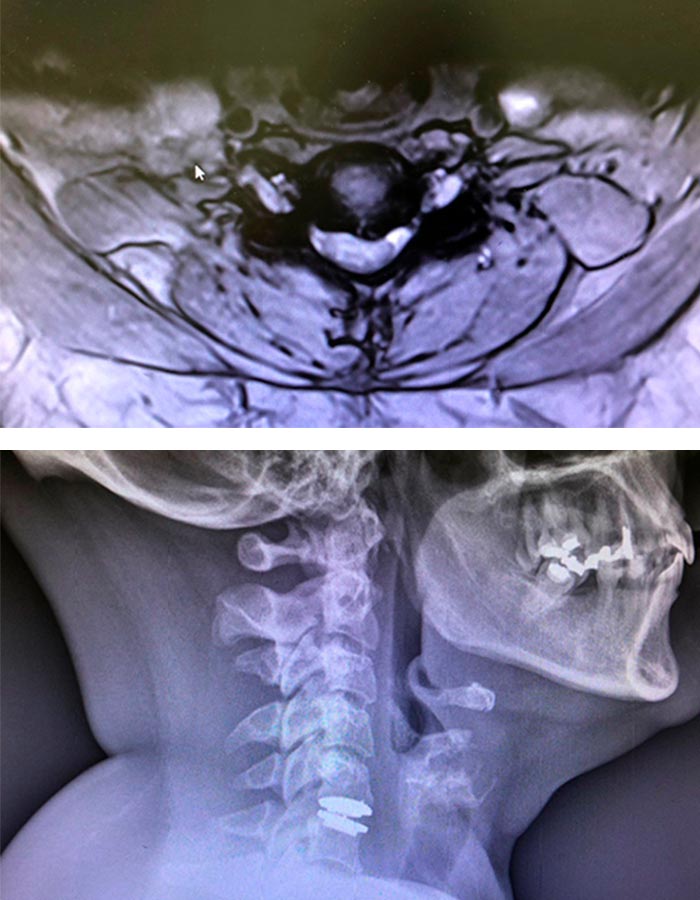

Preoperatorio

Hernia discal cirugia

Hernia discal cuello